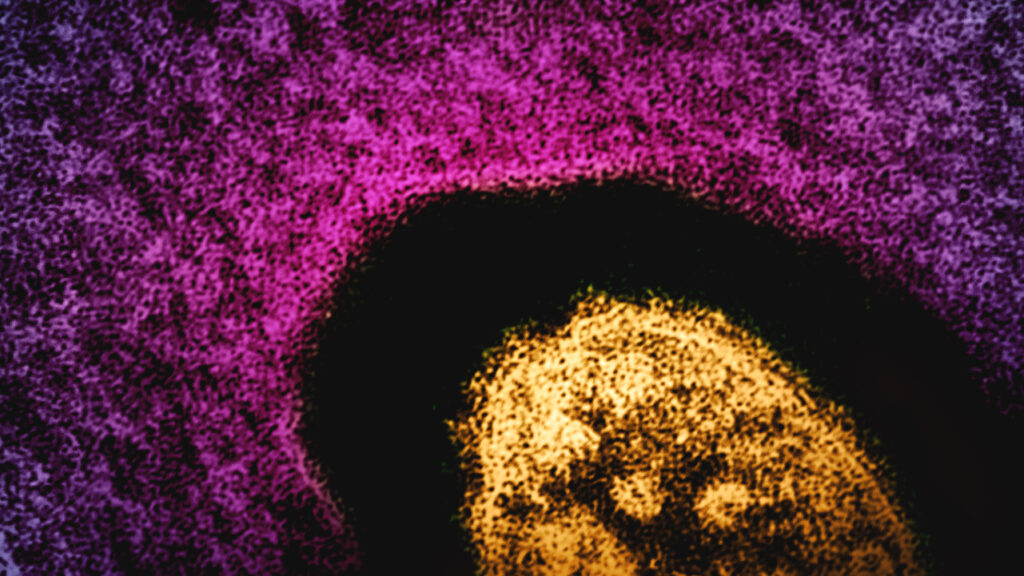

An grownup who was contaminated with measles has died in New Mexico, state well being officers introduced Thursday, although the virus has not been confirmed because the trigger.

Measles is a respiratory virus that may survive within the air for as much as two hours. As much as 9 out of 10 people who find themselves inclined will get the virus if uncovered, based on the CDC.